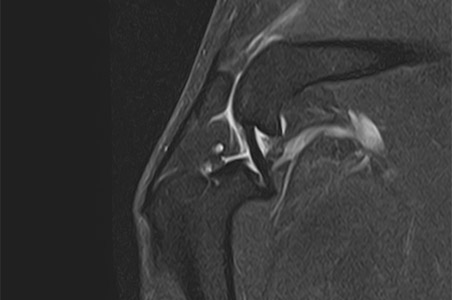

근골격계 MRI

인대 질환 (전십자인대 단열), 연골 질환, 관절염, 관절 종양 등